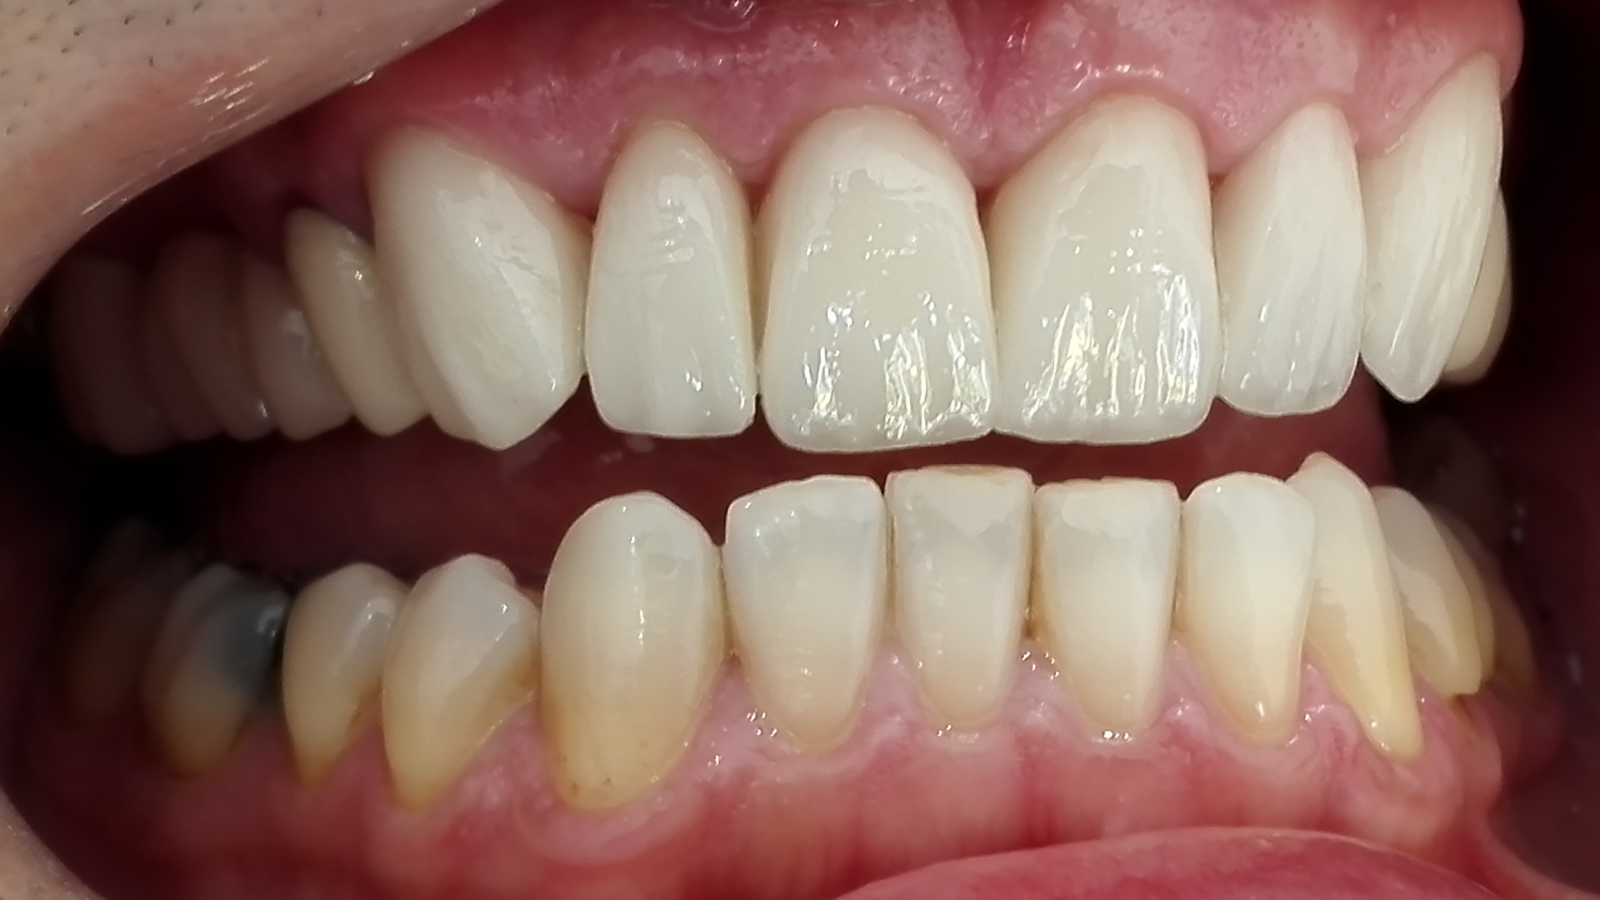

Réhabilitation esthétique après orthodontie : full-zircone & disilicate de lithium

Une jeune patiente arrive en fin de traitement orthodontique pour un déficit esthétique.

La difficulté réside dans la réalisation de prothèses différentes dans le même secteur : jongler avec la full-zircone et le disilicate de lithium.

Ce challenge fut le sujet de mon mémoire du DU d’esthétique de Strasbourg en 2008.

L’expérience et l’investissement dans le digital depuis 2017 rendent le résultat plus prévisible.

Images :